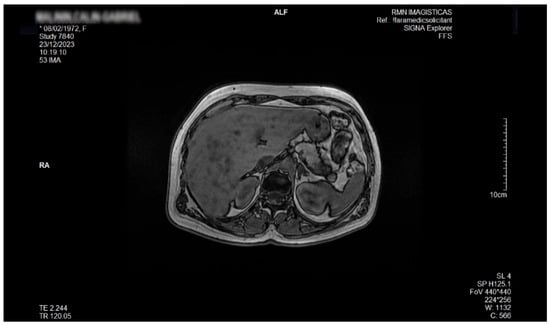

Liver Lipodystrophy in Barraquer–Simons Syndrome: How Much Should We Worry About?

Lipodystrophy is a rare group of metabolic disorders characterized by the abnormal distribution of body fat, which can lead to various metabolic complications due to the body’s inability to adequately process carbohydrates and fat. We report the case of a female, aged 53 years, who was admitted as an outpatient for progressive weight loss of the upper part of the body (face, neck, arms, and chest), dyspeptic complaints, fatigue, mild insomnia, and anxious behavior. Her medical history was characterized by the presence of dyslipidemia, hypertension, and a minor stroke episode. However, she denied any family-relevant medical history. Although the clinical perspective suggested a possible late onset of partial acquired lipodystrophy, due to the imaging exam that revealed an enlarged liver with inhomogeneous structure with multiple nodular lesions, scattered over both lobes, a lot of lab work-ups and complementary studies were performed. Eventually, a liver biopsy was performed by a laparoscopic approach during cholecystectomy, the histology consistent with metabolic disease-associated steatohepatitis (MASH). In conclusion, given their heterogeneity and rarity, lipodystrophies may be either overlooked or misdiagnosed for other entities. Barraquer–Simons syndrome (BSS) may be associated with liver disease, including cirrhosis and liver failure. Liver lipodystrophy in BSS may sometimes feature steatosis with a focal, multi-nodular aspect, multiplying the diagnostic burden. Liver lipodystrophy may manifest as asymptomatic fat accumulation but may progress to severe conditions, representing one of the major causes of mortality in BSS, apart from the cardio-vascular comorbidities. Given the potential of severe outcomes, it is mandatory to correctly assess the stage of liver disease since the first diagnosis. Full article